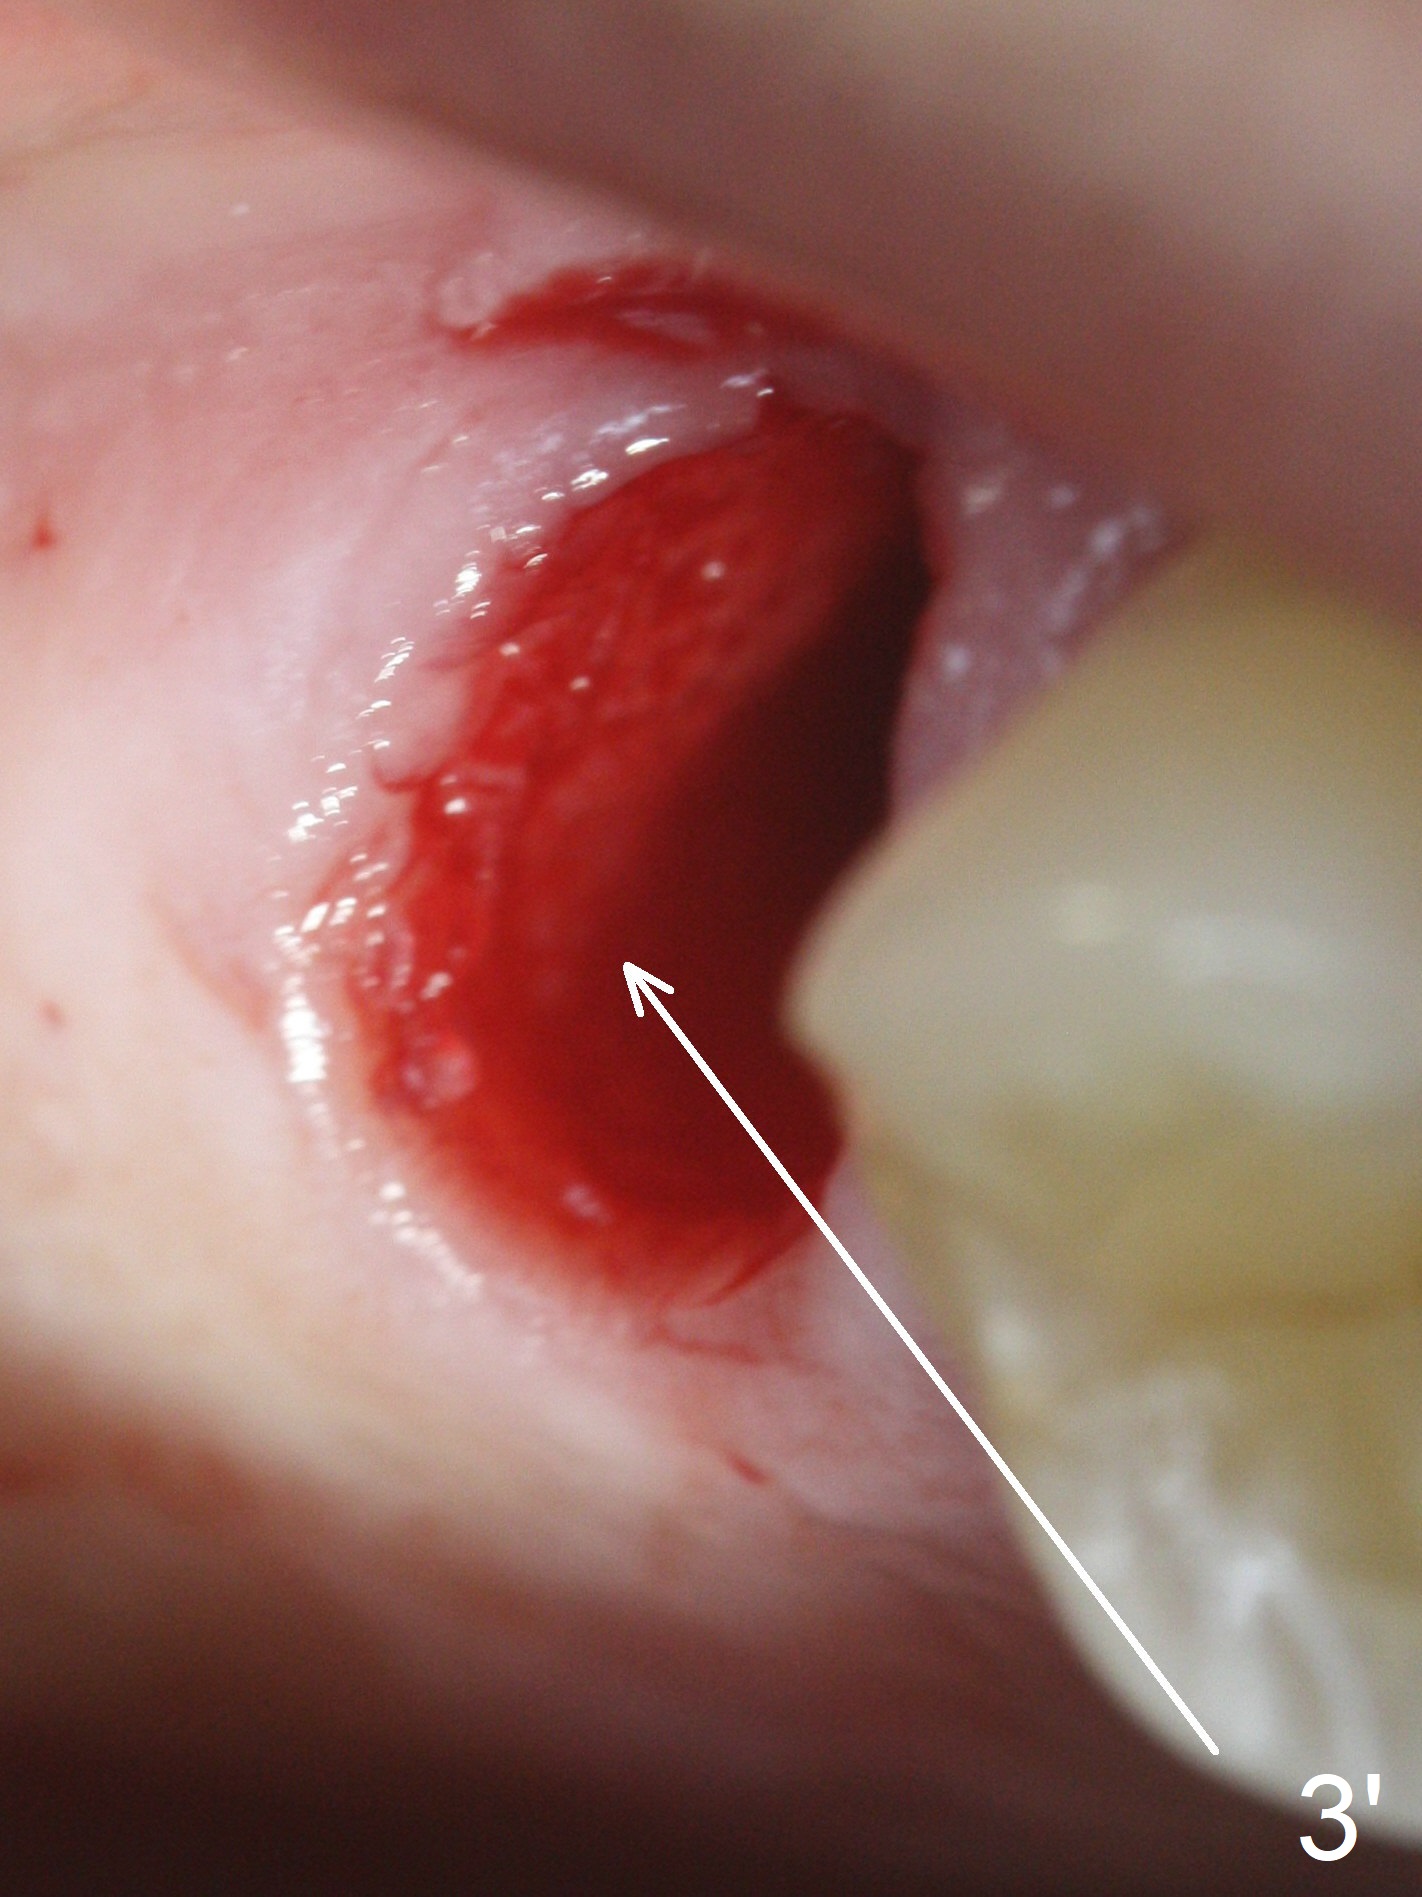

The palatal cusp of the affected 2nd premolar is apparently rotated distal (Fig.1). It is more obvious for the socket (Fig.2): the palatal (P) portion of the socket is more distal than the buccal (B) one. When the gauze is removed (Fig.3), Lindamann bur is used to remove the disto(D)palatal bone of the socket (data not shown), followed by starter drill in the DP wall obliquely (Fig.3'). Once the drill enters the bone for 1-2 mm, the bur is straightened and pushed slightly distal (Fig.3''). Fig.4 shows a parallel pin distal (overcorrect) to the original socket (Fig.4 red dashed line). Sequential osteotomy is conducted until 3.8x13 mm drill for 18 mm (Fig.5): note the 2 steps of the osteotomy (red lines). Since the apical portion of the osteotomy is larger than the drill, a larger implant than expected (5x16 mm) is placed. The implant ends up in the middle of the edentulous area (due to the stepped osteotomy; Fig.6-9; >60 Ncm). Vera allograft is placed (Fig.7-9 *) prior to and after placement of a 6.5x4(3) mm abutment (Fig.8-10). The remaining socket opening is sealed with a piece of Collagen plug (Fig.10 *). The socket is then closed by an immediate provisional (Fig.11 P). The abutment is retightened 2 months postop (Fig.12,13). The crown is cemented 4.5 months postop. Panoramic X-ray and CT are taken nearly 7 months post cementation (Fig.14,15) when the patient is ready for #30 implant guide preparation.